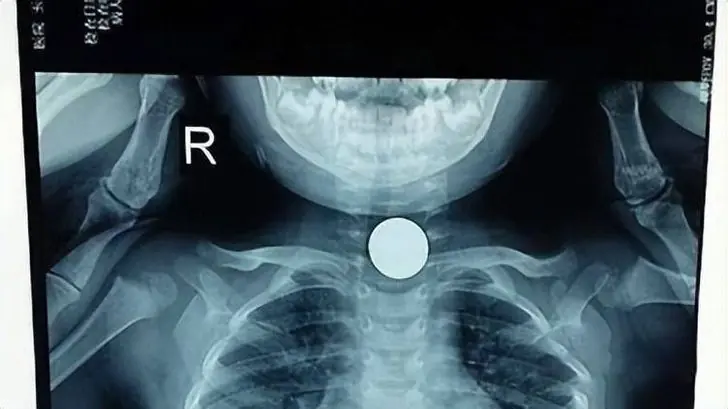

ลู.ก 3 ขวบ อาเจียนฉั.บ หมอเผย "กิน" อะไรเข้าไป แม่ใจสลาย ปรี.ต.บหน้าผัวทันที